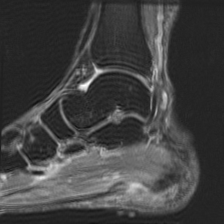

Object Movement

MRI OmniMedVQA Disease Diagnosis

Object Movement - L0 (Original)

L0

L0 (Original)

Question

What is the visual finding in this image?

A Rotator cuff tear B Plantar fascia pathology C Bunion D Golfer's elbow

Ground Truth: B. Plantar fascia pathology